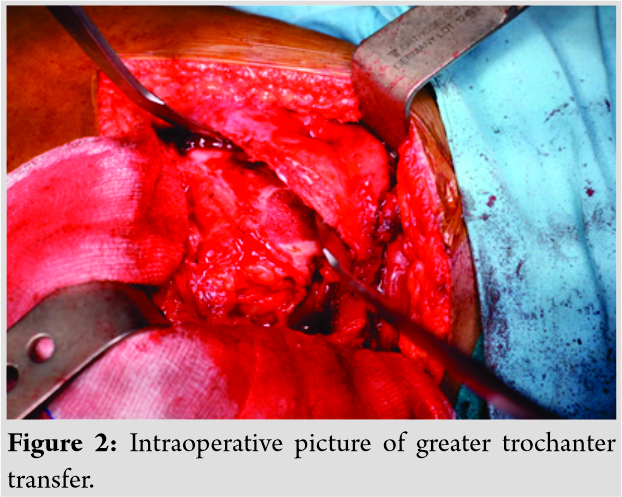

A 13-year-old female patient presented with complaints of painless limp in the right lower limb. The patient had a significant history of septic arthritis of the right hip joint which was managed conservatively in the past. On examination, it was found that the patient had a stable (negative telescopic test) and mobile hip with moderate restriction of abduction (20°). There was no fixed deformity. There was 7 cm of true femoral shortening. The child walked with a Trendelenburg gait with an added component of shortening which was partially compensated by ankle equinus. Radiological investigations revealed severe coxa vara with the steep acetabular inclination and was classified as Choi’s Type 2 septic hip sequel. Based on this workup, it was found that the child was having abductor lurch and femoral shortening, and both needed to be addressed. The patient was put on a lateral position in the operation theater and proximal femur was opened by a posterolateral approach. The hip abductors were carefully identified at their insertion on the greater trochanter (GT) and also the vastus lateralis distally. Piriformis tendon was also carefully identified. A 2 cm thickness of GT with attached abductors proximally and vastus lateralis distally was elevated with an oscillating saw (Fig. 2).  Care was taken to preserve the piriformis attachment on to main femoral fragment. With the help of patella holding clamp, the GT fragment was held and shifted to 2 cm distally and fixed with two 4 mm cannulated cancellous screws. The wound was closed over the suction drain and the patient was then planned for monorail external fixator in the supine position. Gradual distraction was started from the 5th post-operative day (Fig. 3).